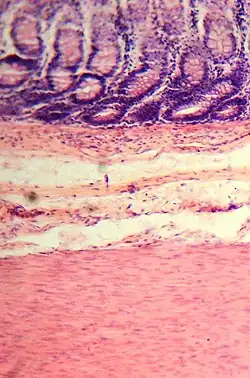

Histological section.

The large intestine absorbs water and any remaining absorbable nutrients from the food before sending the indigestible matter to the rectum.[34] The colon absorbs vitamins that are created by the colonic bacteria, such as thiamine, riboflavin, and vitamin K.[35][36] It also compacts feces, and stores fecal matter in the rectum until it can be discharged via the anus in defecation.